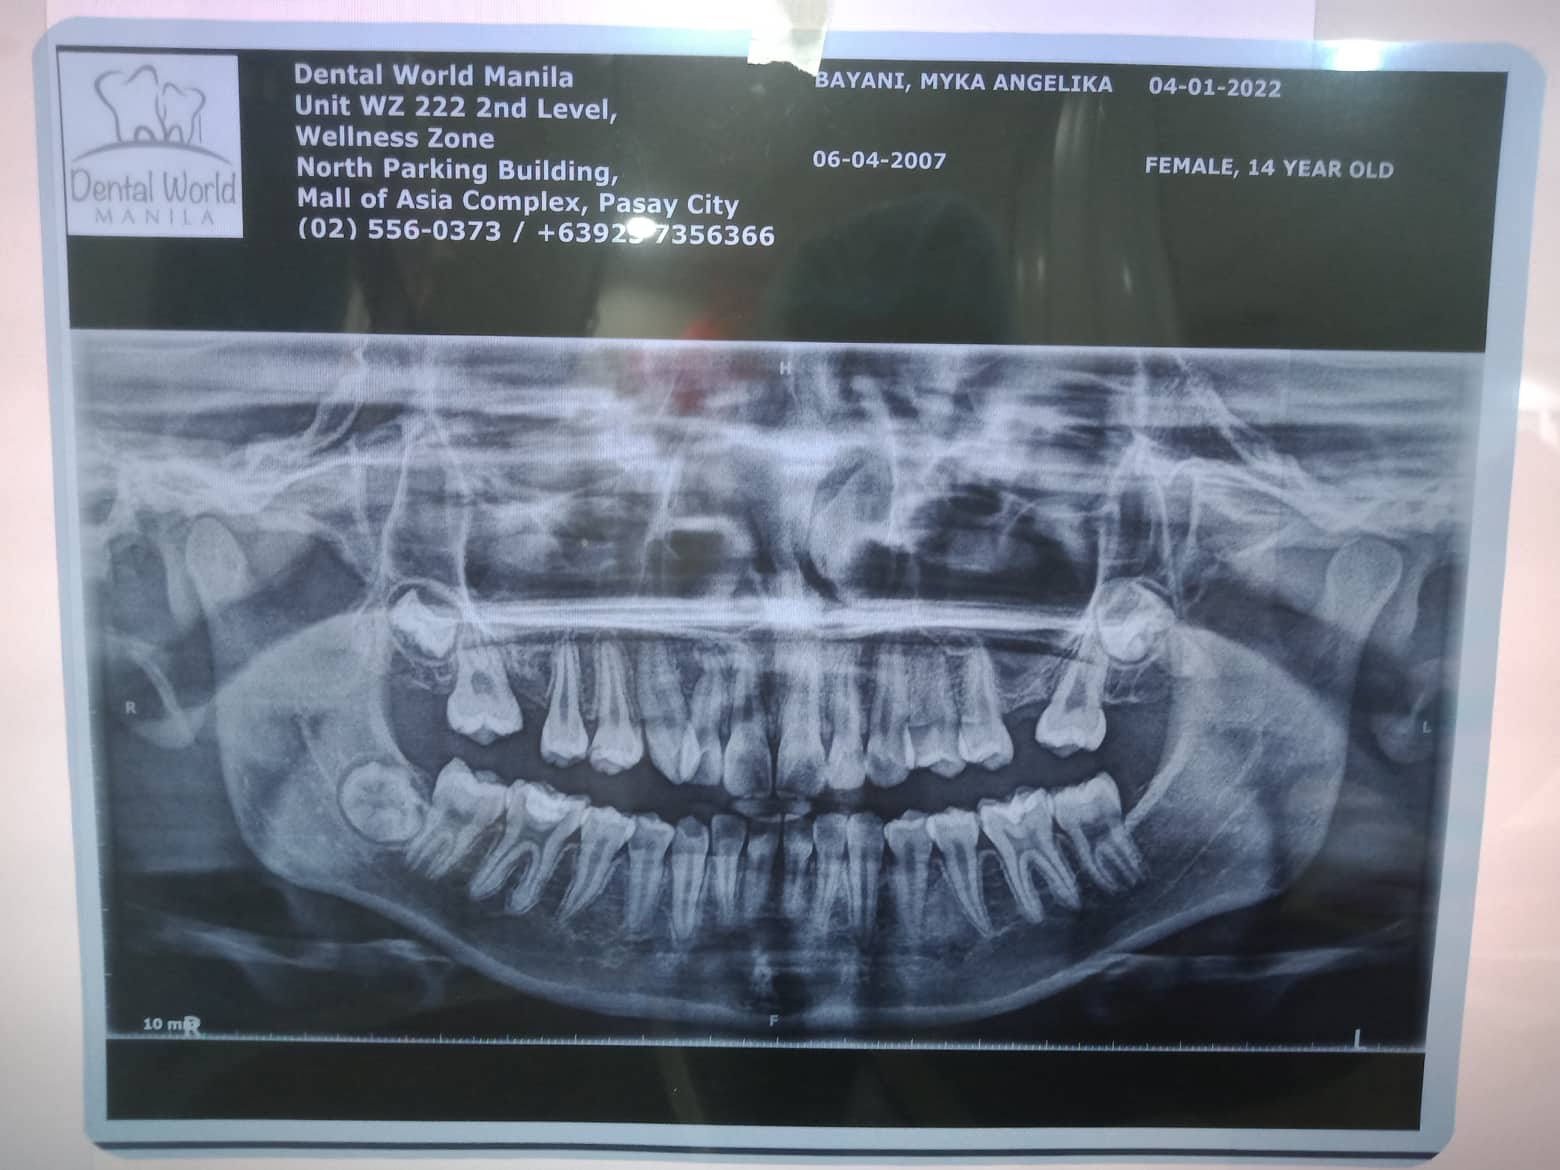

Edit Record Check our patient data records. Add patient information Patient Info Profile picture Last Name First Name Middle Name Birthdate Age Street Barangay City Country Zip Code Contact number Email Procedure 12/08/21- check up ortho free Op/ free 1 filling 02/05/22- MBT .22 slot/ 14 niti UL DP 5999 (less xrays 2400) bal:36 600 ***MB 17/27 03/12/22- 16 niti u/ 14 niti double wiring/ open coil spring/ same wire lower 14 niti 05/07/22- 18 niti U/ 16 ss L reattached 27 RW 13 6/24/22- same wire/ class 2 fox elastic/ 07/06/22- 16ss UL/ class 2 elastic fox 9/24/22- 16X16SS u with hook 22/12 class 2 elastic penguin 11/05/22-adj 12/10/22-adj 01/14/23-adj 05/06/23-U same wire, chain L 16 ss wire, individual #35; reattach bracket 06/10/23- Informed Consent Ortho Adj OP U: Same wire; chain L: 18 ss; chain/Rabbit 07/29/23- 16X22 U SS 16X16 L SS chain 13 to 23 08/26/23- chain U. ind. Lower LC #36- MO - 09/30/23- same wire UL/ reattached 13 fox elastic box 13-23 to 43-44 and 23-24 to 33-34 11/18/23- SAME WIRE; removed echain. placed individual ligaties; pt is deepbite 12/08/23- 16x22 UL chain upper and lower elastic posterior penguin 01/13/24 ADJ same wire chain (removal by march - april) 02/17/24 ADJ same wire 03/23/24 same wire stabilization w ligature wire penguin cross elastics 04/20/24 recall after 3 months #12 D #36 B #26 (no tooth/missing) for fiber reinforced 09/28/24 fiber reinforced #25,#27 11/16/24 LC #27(fiber) 02/01/25 LC #27 Fiber File 302734171_1533036913799406_7265468514337582243_n.jpg File 2 304330217_854772902171076_1144708756641493625_n.jpg File 3 img_20240405_155853.jpg File 4 File 5 File 6 File 7 File 8 File 9 File 10 File 11 File 12 File 13 File 14 File 15 File 16 File 17 File 18 File 19 File 20 Retain Record Retain Record Yes No Save Your Changes